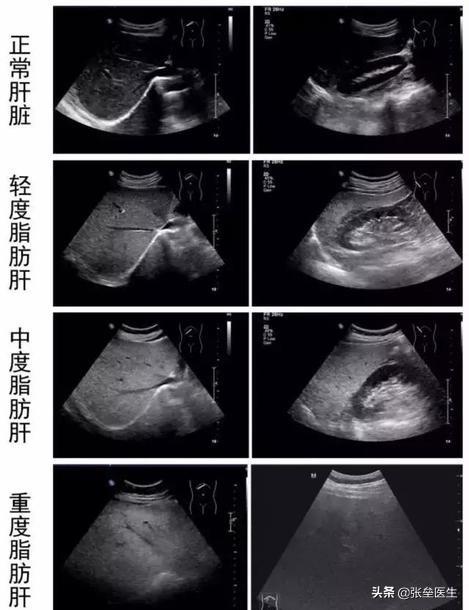

軽度の脂肪肝なのか、重度の脂肪肝なのか、どうやって見分けるのですか?実は、冒頭で述べたように、これは画像診断で報告されている結果でだから主観が多くなる。一般的に言えば軽度の場合超音波検査では、不均一な脂肪肝を認める。肝臓の大きさは正常で、実質のエコー原性は強く、後野は明瞭で、管構造は示され、薄くなっている;ほどほどに超音波検査では、肝容積は大きく、肝縁角は鈍化し、実質エコーは細かく強調され、後方視野でわずかに減弱し、尿細管構造はあまり表示されず、薄くなり、肝臓と腎臓の間に大きなコントラストがある。重症例では、超音波検査で肝臓の形態が充実し、大きさが著しく拡大し、丸みを帯びた肝縁角、雲形に細かく強調された実質エコー、中・後視野の減弱、尿細管構造の表示が乏しく、肝臓と腎臓のコントラストが増大する。